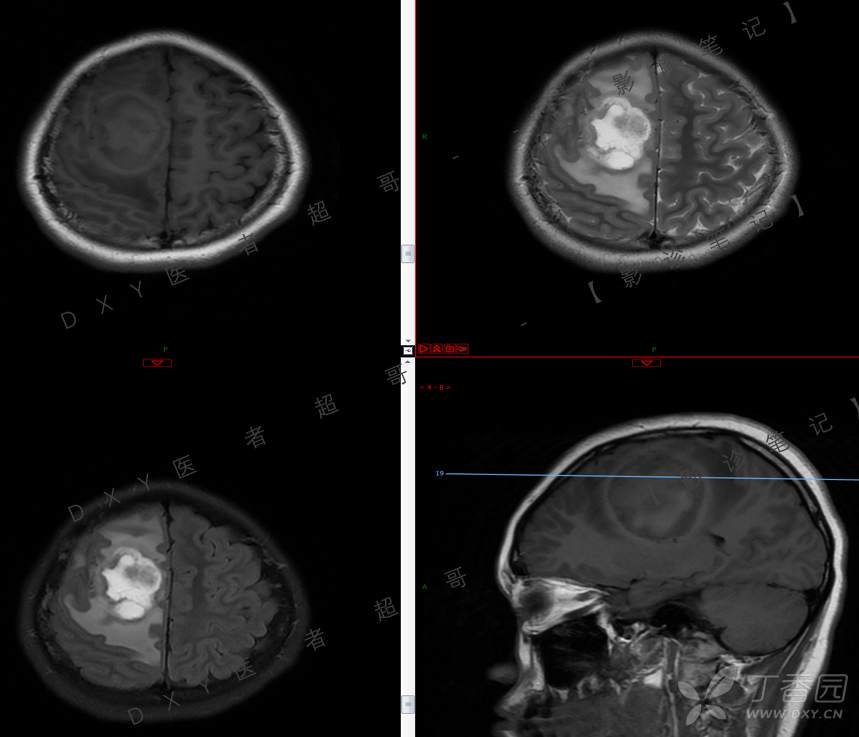

15岁少年,头痛10天,加重伴恶心、呕吐2天,究竟为何?回帖即可查阅病理。

主 诉:头痛10天,加重伴恶心、呕吐2天。

现病史:患者10天前无明显诱因出现头痛,间断发作,无恶心、呕吐,无肢体抽搐等,于当地医院就诊,体温37.4度,予以对症治疗,具体不详,后症状缓解,2天前患者上述症状较前加重,并感双眼胀痛及视物模糊,伴恶心、呕吐,呕吐数次,为胃内容物,再次于当地医院就诊,行颅脑CT考虑“右侧额顶叶病变”,现为求进一步治疗来我院急诊就诊,以“脑脓肿?”收入我科。患者病来精神差,饮食、睡眠欠佳,体重无明显变化。